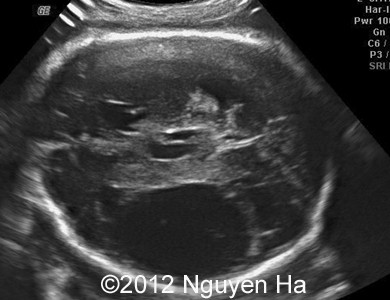

Figure 8-15: 4 days later; image 1-4 suggesting a middle cerebral artery infarction with formation of schizencephaly, no more cortex at the level of the insula.

A 30-year-old woman (G1P0), with unremarkable family history, presented to our unit at 36 weeks of her pregnancy. She did not undergo any previous screening tests. Our examination revealed unilateral hypoechoic inhomogeneous mass within cerebral parenchyma. Our initial diagnosis was teratoma, but repeated exam after four days showed structural changes and different echogenicity of the mass and so our final diagnosis was cerebral hemorrhage. The findings were confirmed by MRI scan.